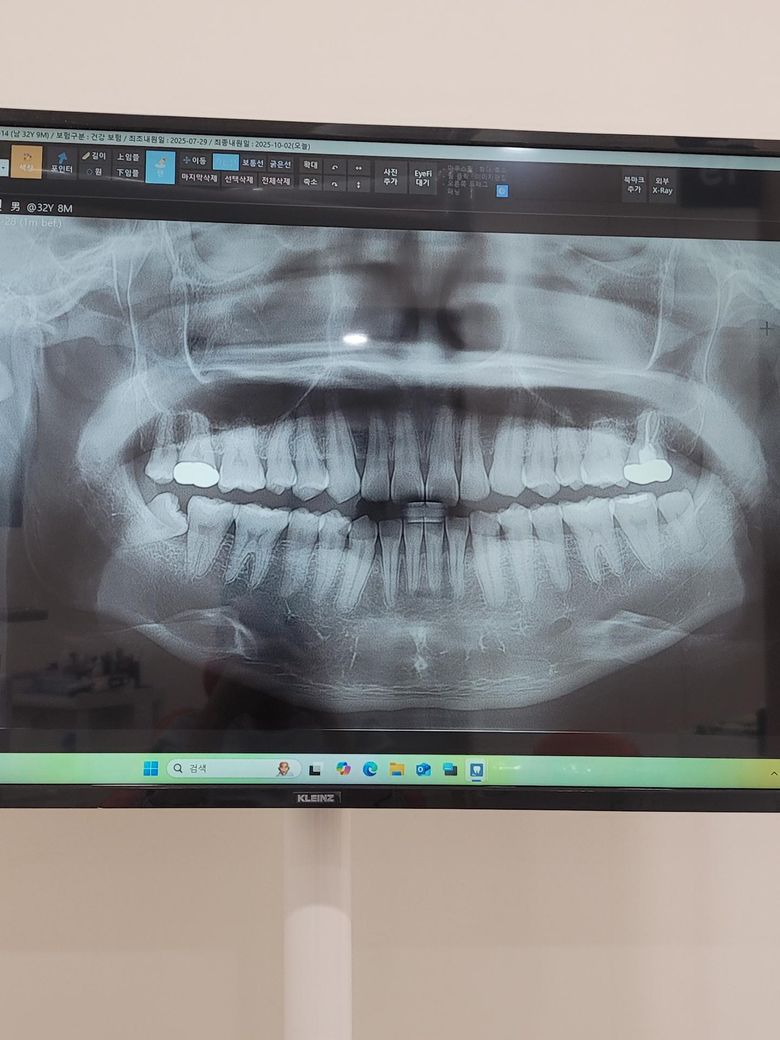

한달전 통증은없었고 치아에 크랙이있대서 신경치료후 크라운씌웠는데요 씌우고나서 뻐근함? 저작해보면 치아가 멍든느낌? 그래서 교합통증인가싶어서 크라운을 갈아내긴했는데 통증이 좀 나아졌지만 여전히 치아 통증이있는데 원인이 뭘까요? 금니로 했습니다 엑스레이상은 문제가없나요? 의사는 원인을 모르겠다네요

차갑거나 뜨거운거에 증상은없는 상태입니다

사진상으로는 특별히 문제가 보이지 않지만 계속해서 불편하면 재신경치료가 필요할 수 있습니다.

엑스레이 상으로는 신경치료가 잘된거 같습니다. 치아에 금이간경우에는 불편감이 조금은 남아 잇을수 잇으니 일단은 조심히 한번 사용해보세요.

방사선 사진상에는 문제가 없어보입니다.

치아에 간 금이 치아 뿌리 까지 진행이 되어 있다면 크라운으로 씌워도 불편감이 있을수 있습니다.

이런경우 치아에 힘을 줄여서 사용을 해야 합니다.

뿌리의 금때문에 불편감이 자주 유발되거나 통증이 있다면 발치를 해야 하는경우도 생길수 있습니다.